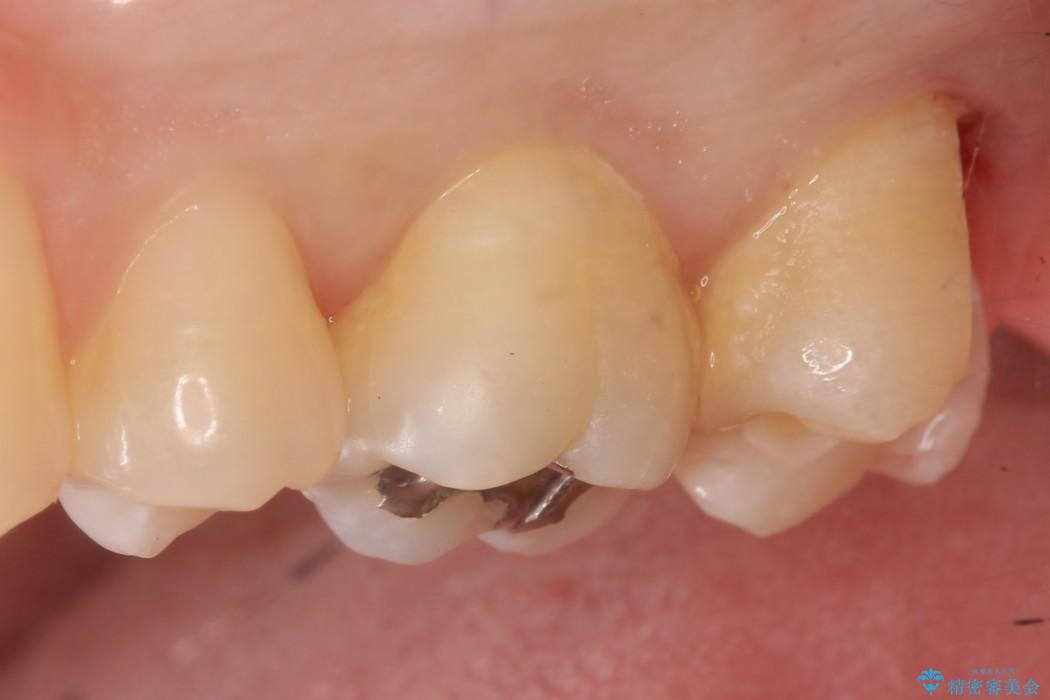

上顎左の一番奥の歯が深い虫歯になって脆くなり、更にその状態に強く噛みしめたわけではない通常の咬合力が加わったことで歯が欠けてしまっていました。

今回は一番奥の歯という位置と、噛み合わせ、清掃状態を加味して適合の高く長持ちするゴールドインレーにて治療することとしました。